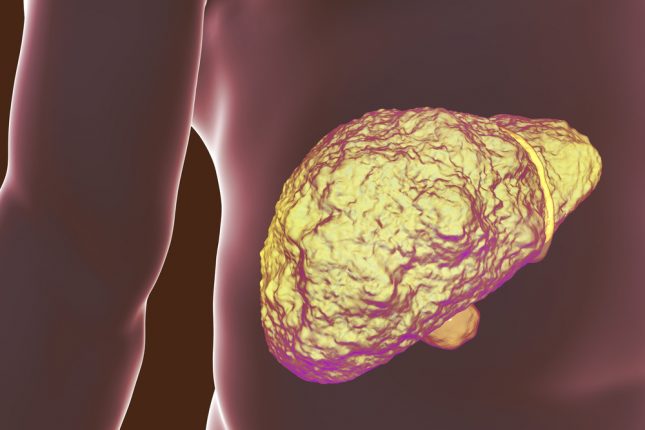

בן 71 התייצג במחלקה עם הלם היפוולמי כתוצאה מקרע של דליות בוושט. הוא סבל משחמת כבד אלכוהולית (Child-Pugh C), תסמונת הפטרינאלית מסוג 2, תרומבוציטופניה, דליות בוושט ופרפור פרוזדורים. הוא היה תחת טיפול באנטי קואגולציה ואמיודרון ללא היסטוריה של מחלת עורקים פרפרית או כלילית. ייצוב המודינמי וטיפול אנדוסקופי בוצע מיד.